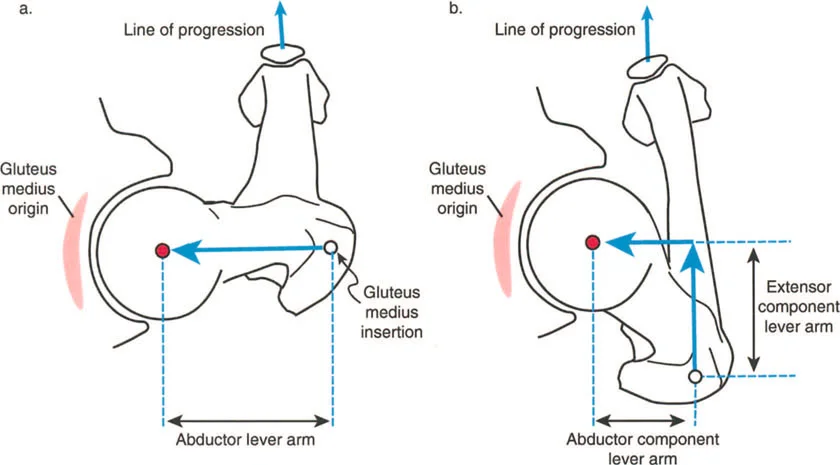

أمثلة أخرى رئيسية للتشوهات الديناميكية تشمل "الورم الفخذي المفرط" (Severe Femoral Anteversion) و "الورك الأفحج" (Coxa Vara). في كلتا هاتين الشذوذات المعمارية، يتم تقصير الطول الفيزيائي لذراع الرافعة لعضلات المبعدة (Abductor muscles) بشكل مرضي بسبب التشوه العظمي نفسه. قد تكون عضلة الألوية الوسطى (Gluteus Medius) صحية تمامًا، ومعصبة جيدًا، وقادرة على توليد قوة بيولوجية طبيعية، لكنها تعاني من خلل وظيفي سريري عميق لأن ميزتها الميكانيكية قد سُلبت بسبب الهندسة الهيكلية المتغيرة. هذه الفئة الفرعية المحددة من الأمراض تُعرف باسم "تشوه في طول ذراع الرافعة".

بشكل خاص، يصف خلل وظيفة الذراع الرافعة حالة سريرية تتشوه فيها أذرع الرافعة الداخلية و/أو الخارجية بسبب سوء محاذاة العظام، أو التشوهات الالتوائية، أو تيبسات المفاصل الموضعية.

بينما لا يستطيع الطب الحديث فعل الكثير لزيادة القوة البيولوجية الخام التي تولدها العضلة بشكل دائم (بخلاف العلاج الطبيعي)، يمكن غالبًا زيادة حجم العزم المؤثر على المفصل بشكل كبير ببساطة عن طريق تصحيح خلل وظيفة الذراع الرافعة جراحيًا. هذا هو جوهر النهج الذي يتبعه الأستاذ الدكتور محمد هطيف في علاج التشوهات العظمية المعقدة، حيث يركز على استعادة الميكانيكا الحيوية السليمة للجسم.

- الورك الأفحج (Coxa Vara): تشوه خلقي أو تطوري في عظم الفخذ يؤدي إلى تقصير ذراع الرافعة لعضلات الورك المبعدة، مما يضعف قدرتها على تثبيت الحوض.

- عرج ترندلنبورغ (Trendelenburg Lurch): في حالات ضعف عضلات الورك المبعدة (مثل الورك الأفحج)، يميل الحوض إلى السقوط على الجانب المقابل أثناء الوقوف على ساق واحدة، مما يؤدي إلى مشية متمايلة.